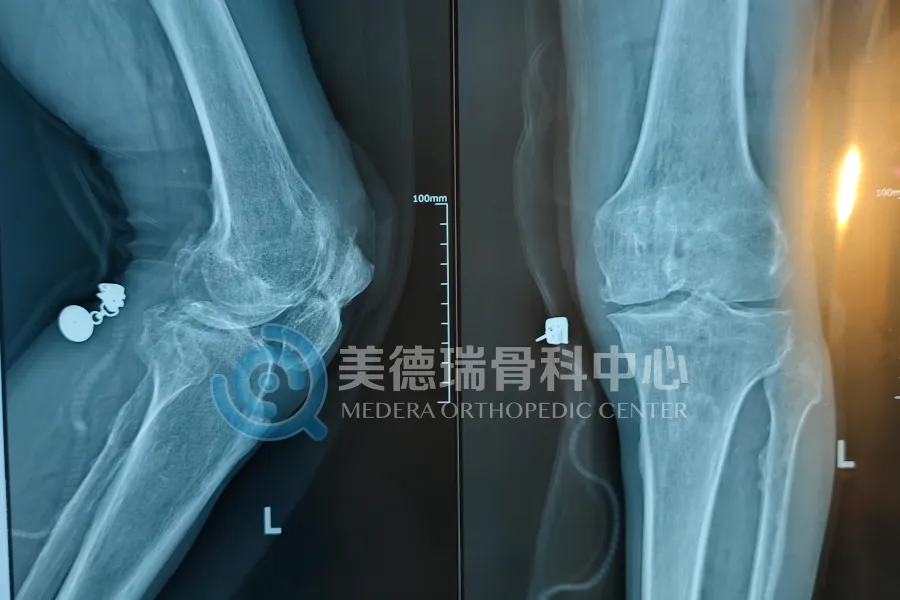

此次接受治疗的患者是一位年逾七旬的老人,两年前做过髌骨骨折手术。最近半年,他的左膝前方反复流脓,走路时创口总是发红、肿胀,甚至连基本活动都成了负担。原本在外院已经取出过克氏针跟钛缆,也缝合过伤口,但还是没能好转。

表面看,这是一次“术后感染拖着没愈合”;但手术中打开来看,问题远比想象复杂:整个创口约10公分长,髌骨几乎整个表面外露,骨面已出现明显的感染改变,表现为发黑、变硬,并被大片炎性坏死组织覆盖,周围软组织缺损严重,已无法实现直接关闭创面。连原先置入髌骨的克氏针孔内,也可见脓液渗出。换句话说,这不是创口没养好,而是感染已经深入骨头内部,发展为髌骨骨髓炎——一种临床少见、且目前缺乏统一有效标准治疗方案的骨感染类型。